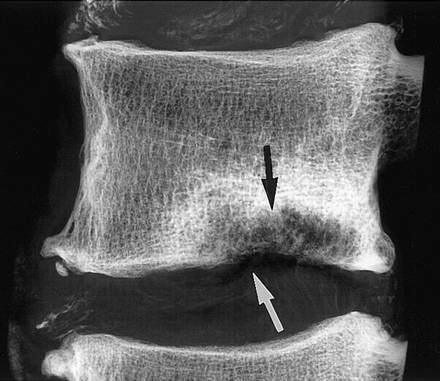

Грыжа Шморля относится к рентгенологическим признакам дефекта позвоночника и врожденному анатомическому нарушению, что никак не влияет на функциональную возможность позвоночника и жизнь человека в целом.

Подтверждение диагноза и лечение

Выявляется такой порок при рентгенологическом исследовании, КТ и МРТ. Лечение консервативное или хирургическое. С помощью медикаментозной терапии устраняют болезненность, дискомфорт, воспаление. Больному назначаются нестероидные противовоспалительные средства, анальгетики, проводится блокада позвоночника. Дополнительно показана физиотерапия, массаж, иглорефлексотерапия, мануальное лечение, ЛФК и упражнения в воде.